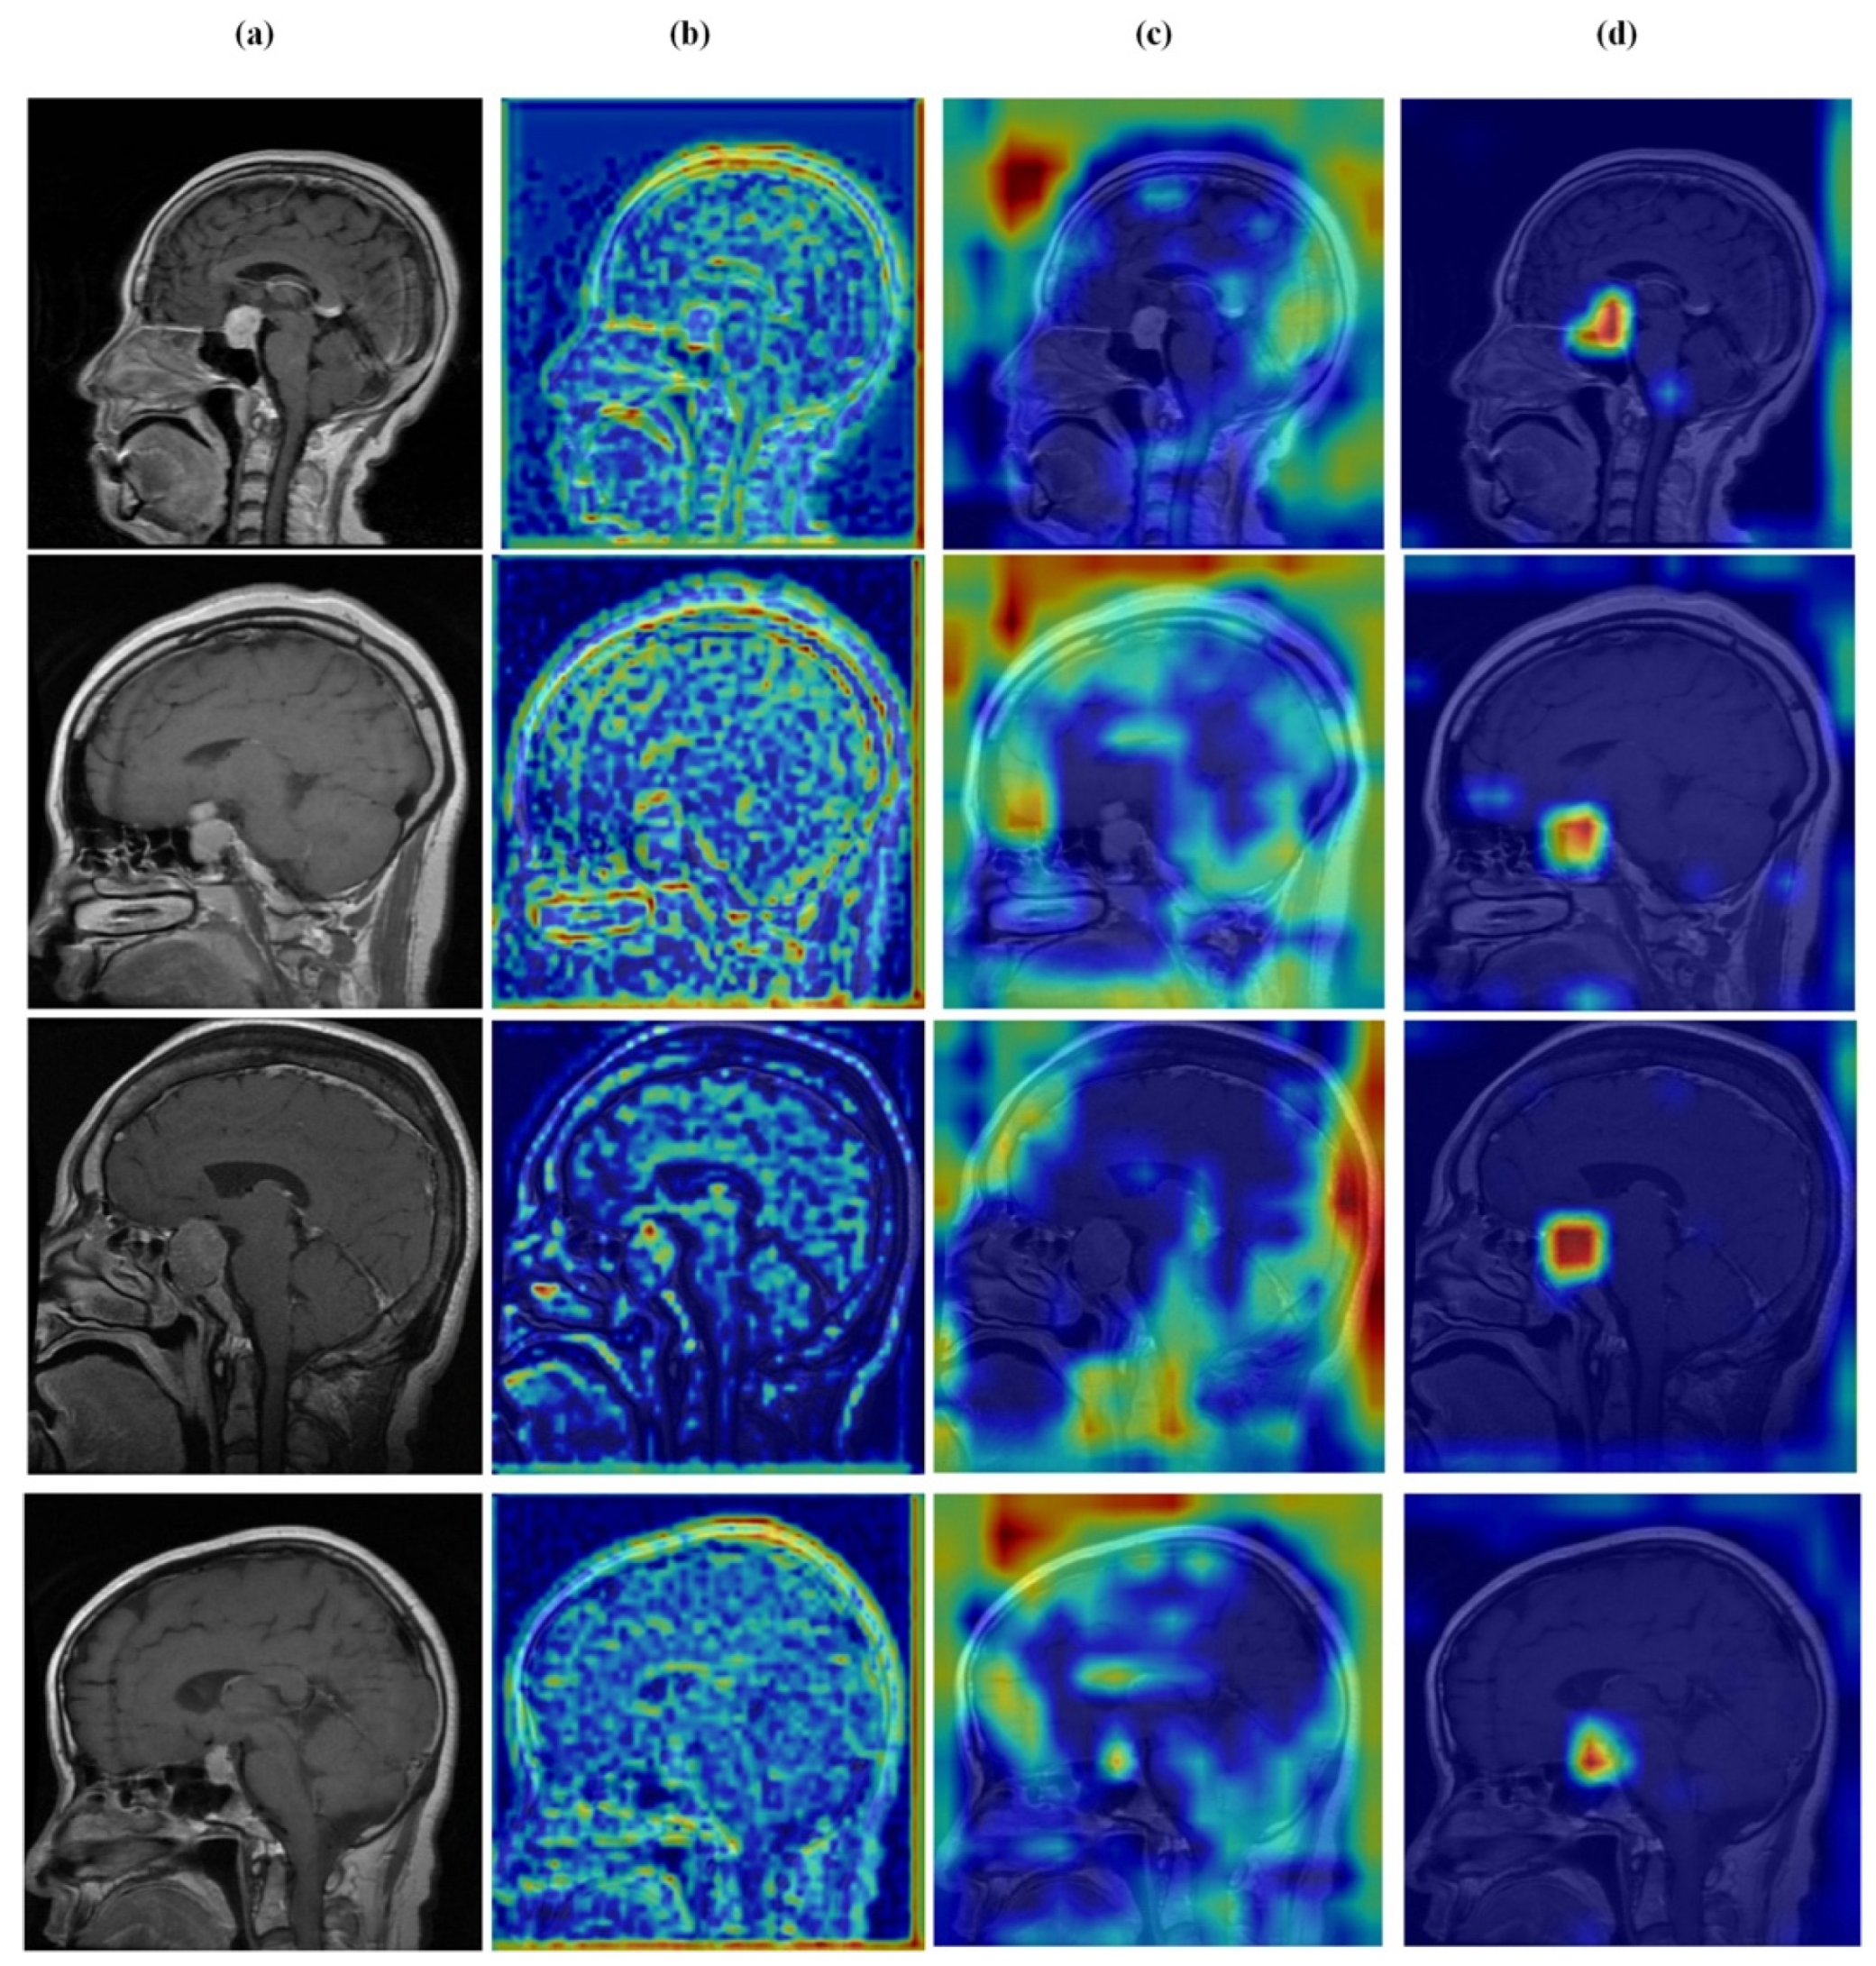

4.7. Feature Learning Analysis

Figure 12, Figure 13, Figure 14 and Figure 15 present Grad-CAM visualizations that trace the hierarchical feature learning of the proposed model across the four classes. Columns are organized as (a) input, (b) high-level features, (c) mid-level features, and (d) low-level features. In (d), the network emphasizes primitive cue edges, intensity transitions, and fine textures capturing sulcal boundaries, skull edges, and generic tissue patterns. Progressing to (c), activations become more structured and context-aware, highlighting coherent anatomical regions and diffuse hyperintense areas that provide spatial context for lesion localization. At (b), class-discriminative focus emerges with responses that contract tumor-centric hotspots for glioma and meningioma and to the sellar region for pituitary cases, while no_tumor images exhibit suppressed high-level responses, reflecting the model’s rejection of false lesion cues. This bottom-to-top progression from generic edges to task-specific evidence explains the model’s improved decision reliability and aligns with the multi-task design that encourages precise, clinically meaningful attention.

Figure 14.

Visual representation of feature activations in meningioma tumor cases. (a) input, (b) low-level features, (c) mid-level features, and (d) high-level features.

Figure 15.

Visual representation of feature activations in pituitary tumor cases. (a) input, (b) low-level features, (c) mid-level features, and (d) high-level features.